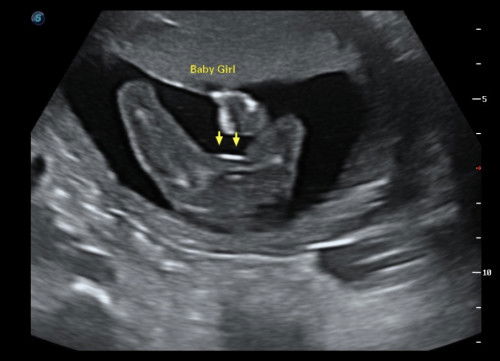

Hi mommies! Im 1st time mom. Saya dah rasa kicks/movement since 21 weeks lagi. This week dah 26 weeks, kalau government punya klinik dia tak suruh kira lagi kan, tapi saya tetap kira. Contoh harini saya tak rasa banyak kicks, so saya jadi overthinking, baby ok ke? Kenapa baru 3 rasa kicks. Apa pendapat mommiess??#firstmom